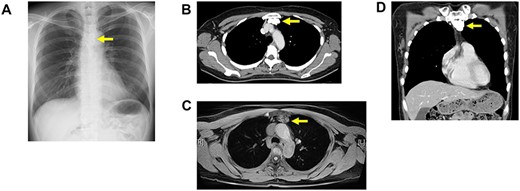

A 49-year-old woman was admitted to the hospital presenting with a productive cough. The patient had no past medical history of note excluding a pneumothorax surgery in her twenties, and blood examinations were normal. Chest radiography showed an abnormal shadow in the anterior mediastinum (Fig. 1A), and chest computed tomography showed a 40-mm tumor with massive calcification in the anterior mediastinum (Fig. 1B and C). Magnetic resonance imaging (MRI) showed T1-weighted and T2-weighted heterogeneous signal intensities (Fig. 1D). Preoperative differential diagnoses were hamartoma, teratoma, calcified lymph node, hemangioma or thymic tumor with calcification. Excision of the tumor was performed using video-assisted thoracoscopic surgery, but intraoperative pathological diagnosis was difficult due to massive calcification and ossification. The tumor measured 40 × 40 mm with almost all parts showing calcification and ossification. Hematoxylin and eosin staining revealed calcification with focal round and oval cells and lymphocytes (Fig. 2A). An immunohistochemical analysis revealed that round and oval cells were positive for AE1/3, CAM 5.2 and negative for CD5 (Fig. 2C and D). The lymphocytes were CD3-positive immature T cells, and the tumor was diagnosed as type B3 thymoma.

(A) Chest X-ray showing a calcification tumor in anterior mediastinum (arrow). (B) A chest computed tomography scan of horizontal section showing a 40-mm calcification tumor in anterior mediastinum. (C) A chest computed tomography scan of coronal section showing a 40-mm calcification tumor in anterior mediastinum. (D) MRI scan showing T1-weighted heterogeneous signal intensities.